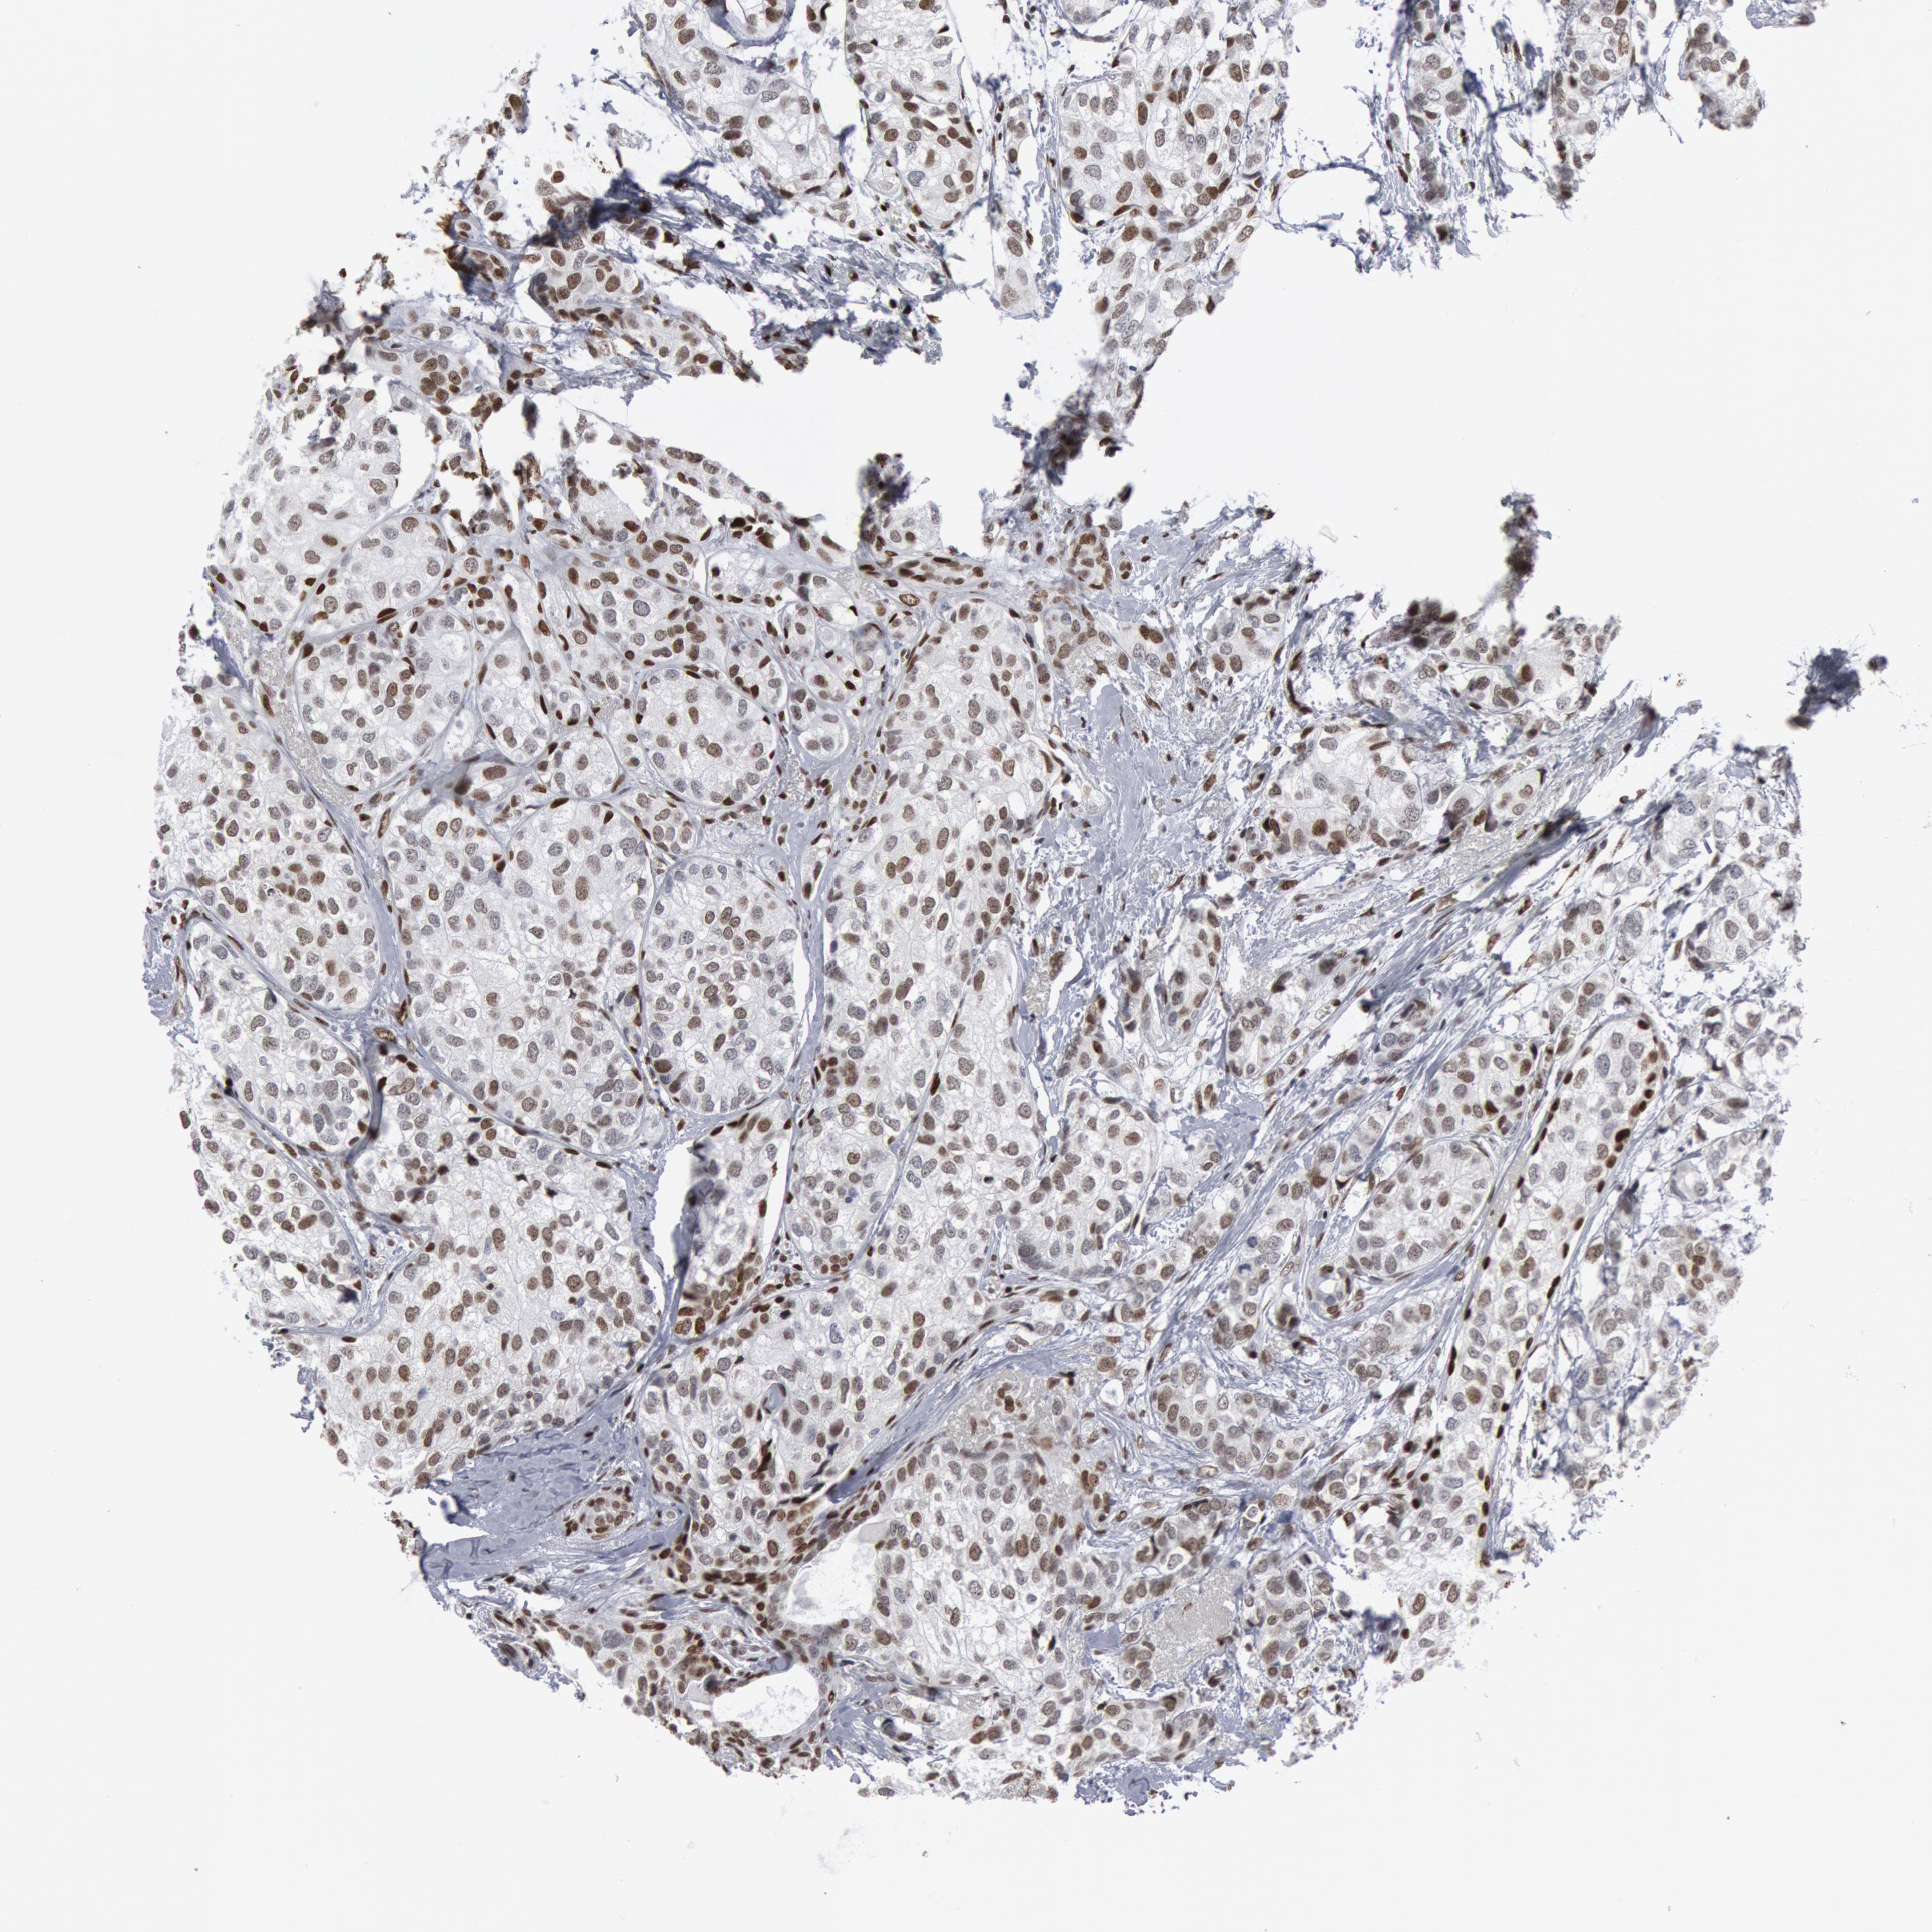

CANCER BREAST CANCER Show tissue menu

BRCA TCGA BRCA VALIDATION PROTEIN EXPRESSION

Breast cancer

Human cancer

Breast invasive carcinoma